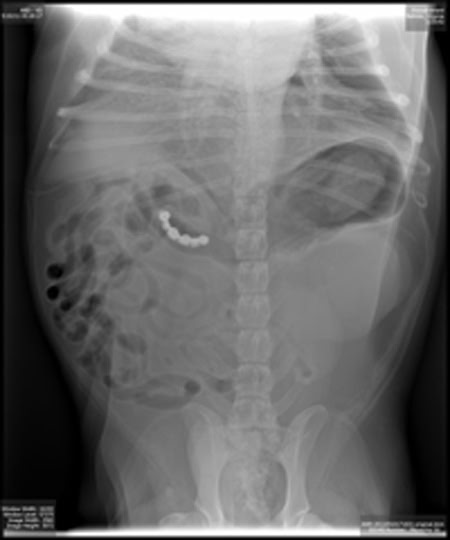

優勝写真:

犬が飲み込んだナインボールズ

この画像を大きなサイズで見る